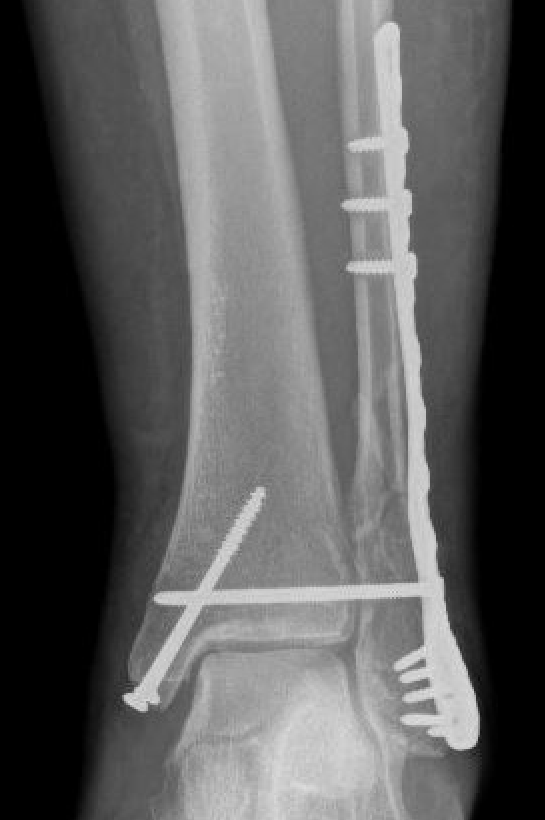

Medial malleolus + Weber C lateral malleolus

| Fibula | Medial Malleolus | Syndesmosis |

1. Interfragmentary lag screw + neutralisation plate

2. Locking plate |

2 partially threaded lag screws Tension band wire Plate |

Open reduction of syndesmosis Stabilized with screws / tightrope |